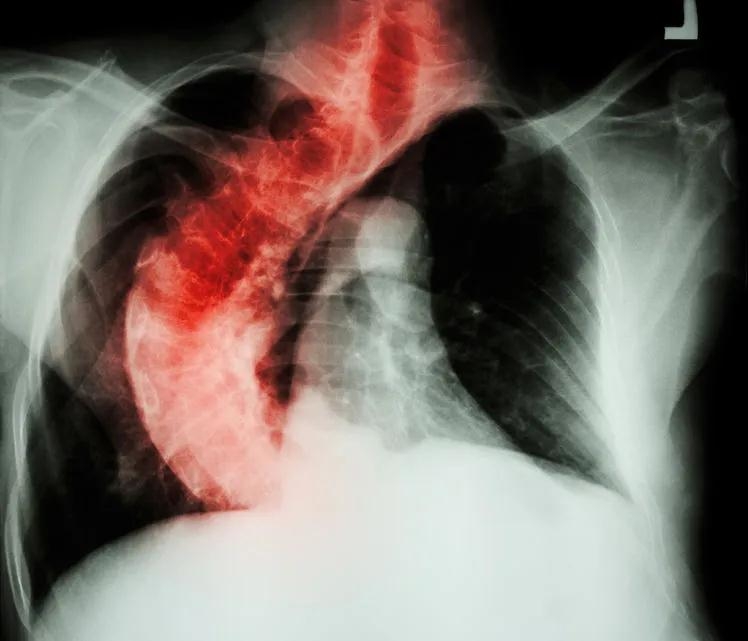

临床观察中发现,多数脊柱侧凸患者因胸廓畸形受限而存在不同程度的呼吸功能受限,表现在走路、上下楼梯等日常轻微活动中即会出现气短气促。

脊柱侧凸常引起胸廓的畸形与运动异常:

(1)胸廓畸形使胸腔容积缩小,使肺实质受压,肺容积缩小,影响肺充气;

(2)气道受压弯曲,使肺通气受阻,肺活量与呼吸流速下降;

(3)双侧胸廓运动不对称,使肺下界移动度减低,前后径扩张受限;

(4)影响呼吸系统发育:若在婴幼儿时期开始出现脊柱侧凸与胸廓畸形,则会导致肺脏发育异常,肺泡增殖减少,在儿童或青少年时期开始出现侧凸的患者,肺泡的大小和功能也会受到影响。同时,肺血管数量随着肺部发育不良也减少。

综合以上原因,脊柱侧凸患者会并发呼吸功能损害。

青少年及较年轻的患者多数是由脊柱侧凸导致胸廓畸形,进而造成限制性通气功能障碍。

成人脊柱侧凸由于肺脏受压,肺泡舒张长期受限,造成肺血气体交换异常,常表现为限制性通气功能障碍与弥散功能障碍混合的肺功能损害。